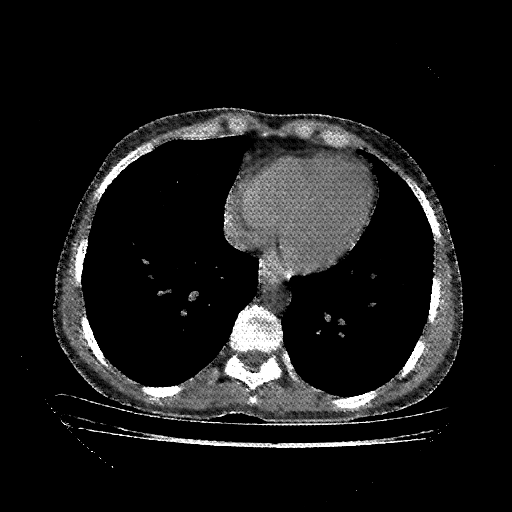

Targeted Slice 70 - Mediastinum Window Analysis (Generated vs Real Venous)

0.778

Mediastinum SSIM

42.9

Mediastinum RMSE

15.0

Mediastinum MAE

Average Mediastinum Window Metrics Across All Slices (112 slices) - Generated vs Real Venous

0.723

Mediastinum SSIM (Avg)

45.5

Mediastinum RMSE (Avg)

18.0

Mediastinum MAE (Avg)

Original VENOUS CT scan

No window - Raw intensity values

Mediastinum window (WL 40, WW 400 β†’ Low βˆ’160, High +240)